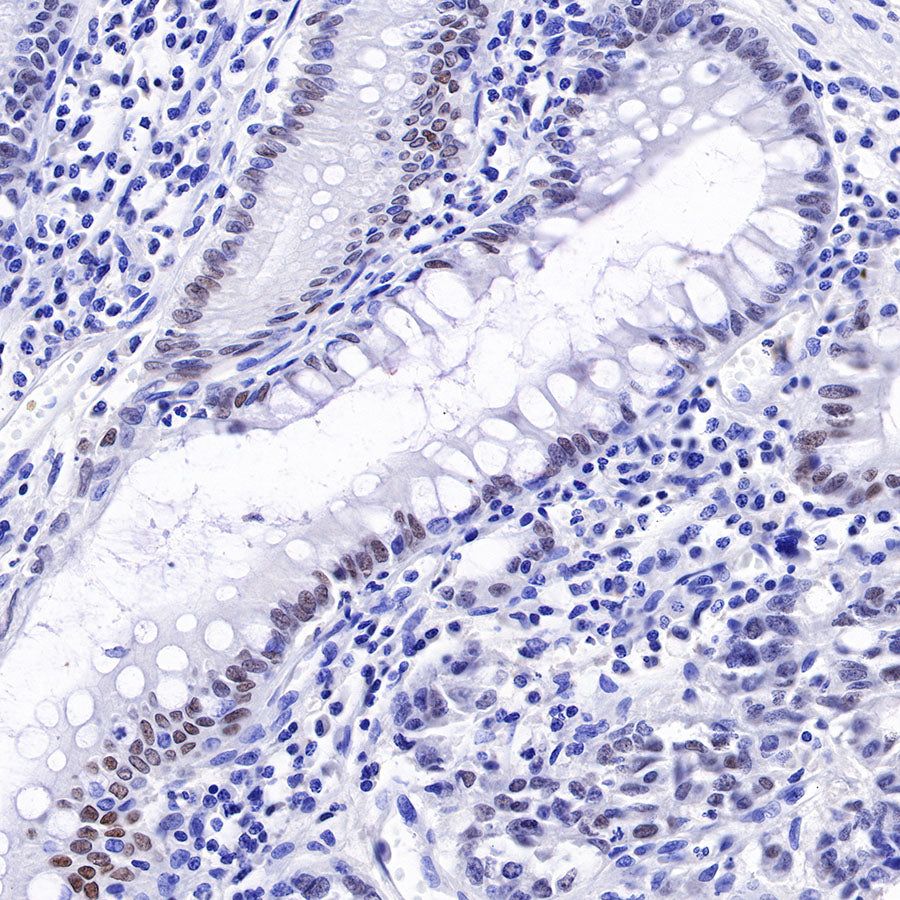

Immunohistochemistry

IHC shows positive staining in paraffin-embedded human colon. Anti-HNF4α antibody was used at 1/500 dilution, followed by a HRP Polymer for Mouse & Rabbit IgG (ready to use). Counterstained with hematoxylin. Heat mediated antigen retrieval with Tris/EDTA buffer pH9.0 was performed before commencing with IHC staining protocol.